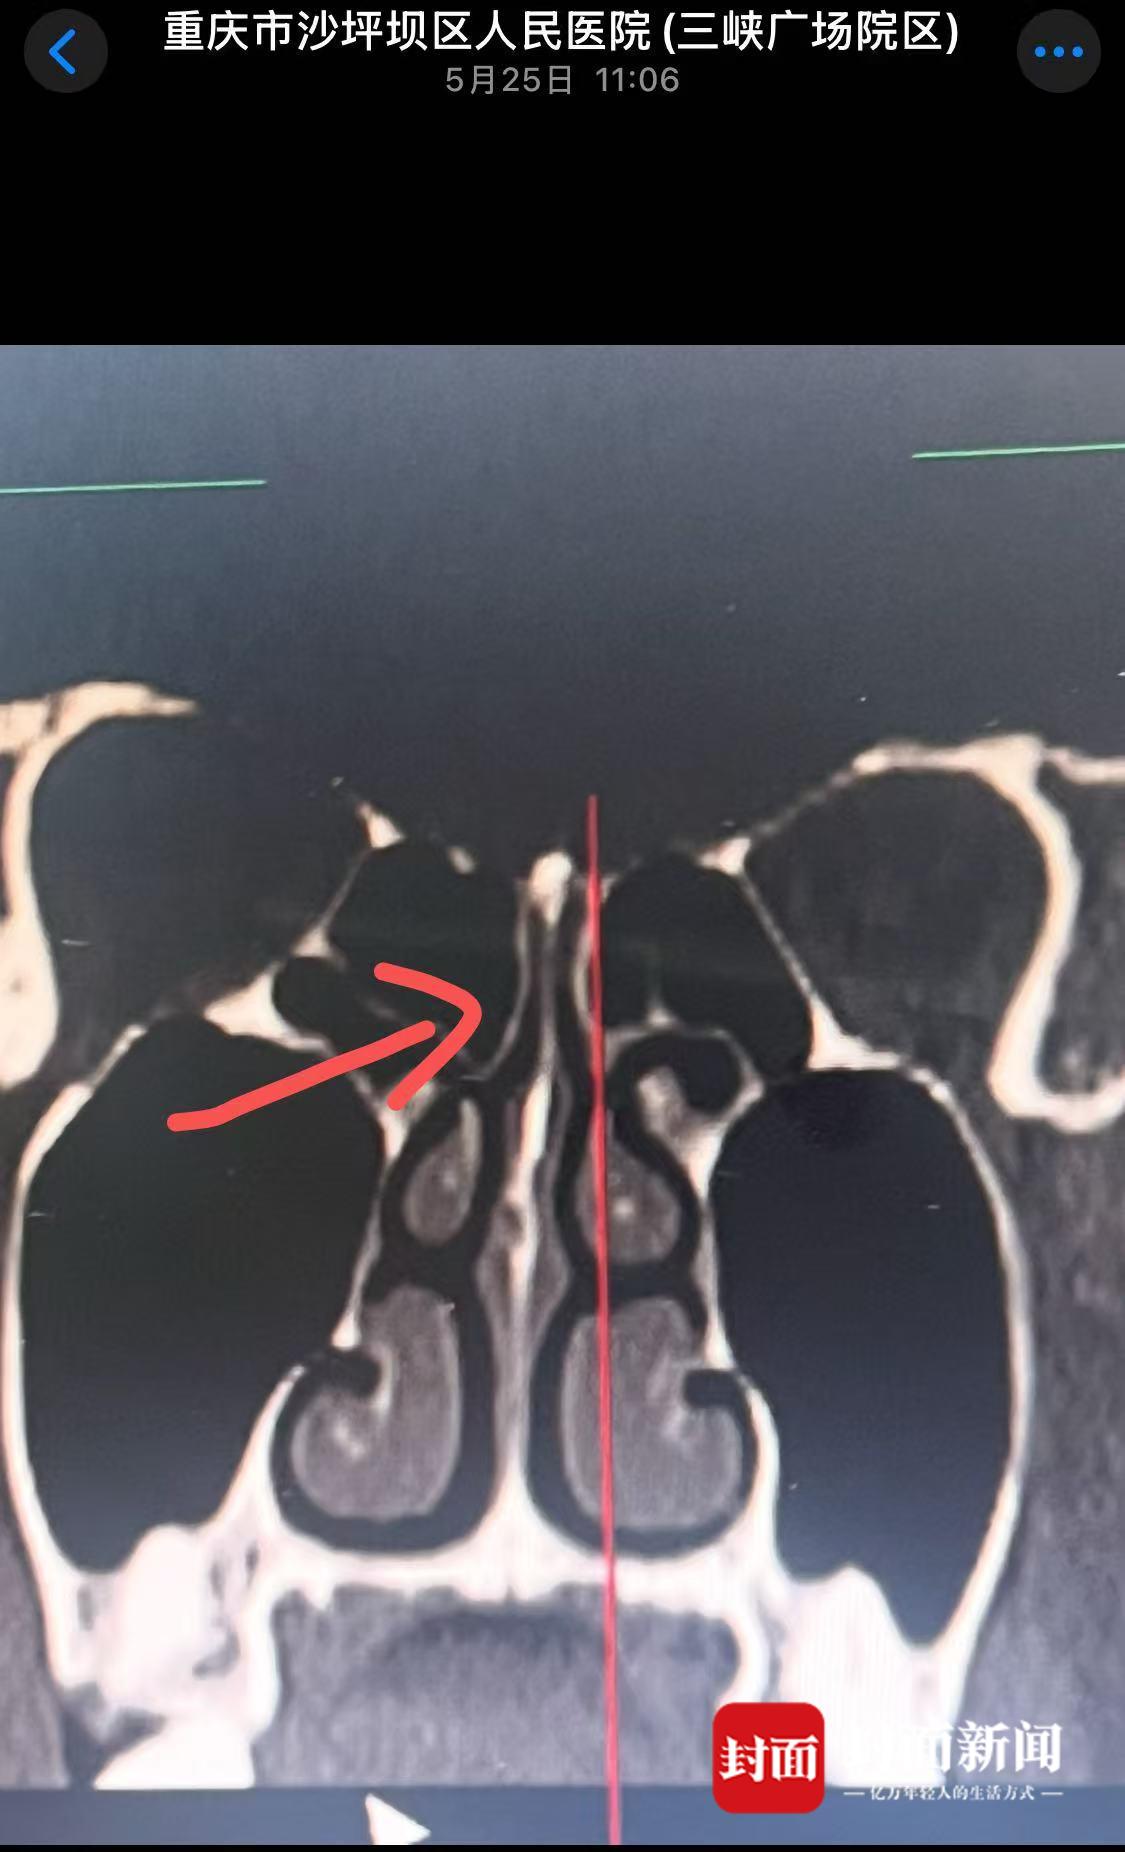

“王某先后对我动手了5次。”刘先生表示,其中一次,王姓女子抢夺手机后,将手机狠狠砸向他的面部,导致其鼻梁骨骨折,面部多处受伤,“当时满脸都是血。”

刘先生鼻梁骨折,还未恢复完好。

刘先生还表示,至今他已花了2万多元的医疗费,鼻子也未完全恢复,后期还需要进行整形手术 。